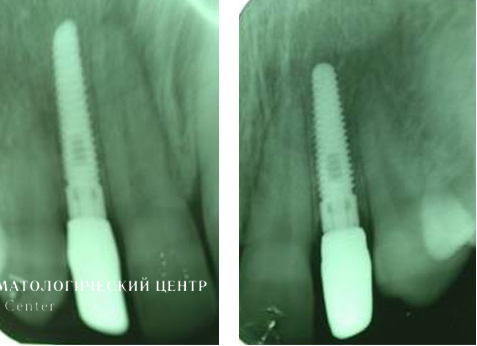

Для устранения эффекта серой, синюшной десны выполнены эстетические безметаллловые оксидциркониевые реставрации. Представленные рентгенограммы демонстрируют успешную имплантацию и максимальную точность прилегания конструкции, а иллюстрации после окончания лечения убеждают в гарантированном достижении желаемого эстетического результата, в частности в наиболее сложной с точки зрения геометрии эстетики десневой зоне.